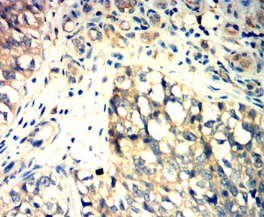

IHC    1/200 - 1/1000